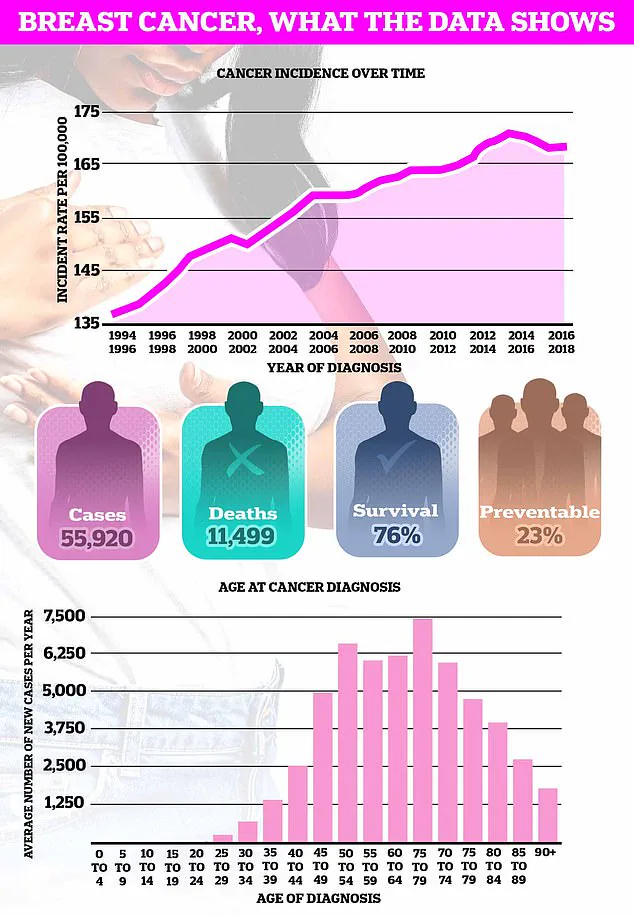

Breast cancer, the UK’s most common cancer with nearly 56,000 new cases diagnosed annually, is now being viewed through a lens that includes not just genetics and environmental toxins, but also reproductive history and metabolic health.

The charity Cancer Research UK estimates that almost one in 10 of Britain’s nearly 60,000 annual breast cancer cases are caused by being overweight or obese.

This statistic underscores the growing public health challenge posed by rising obesity rates.

The fresh research comes at a time when obesity rates in Britain have continued to grow.

Just this week, official data revealed nearly two-thirds of all adults in England are either overweight or obese.

This epidemic, coupled with the rising average age of first-time mothers—now 31, almost five years higher than in the mid-70s—creates a dual challenge for public health officials.

Breast cancer is the most common cancer diagnosed in the UK each year, accounting for a sixth of all cases and claiming over 11,000 lives each year.

Survival rates for breast cancer vary depending on what stage it is diagnosed but, overall, three out of four women are alive 10 years after their diagnosis.

This marked improvement in survival rates is a testament to advancements in early detection, treatment protocols, and patient care.

Breast cancer survival has doubled in the last 50 years in part thanks to regular screening and increased awareness of symptoms.